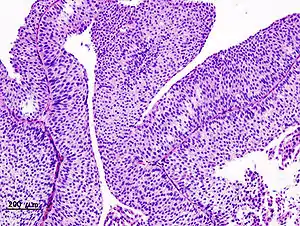

| Histopathology of transitional carcinoma of the urinary bladder. Transurethral biopsy. Hematoxylin and eosin stain. | |

Histopathology of urothelial carcinoma of the urinary bladder, showing a nested pattern of invasion. Transurethral biopsy. Hematoxylin and eosin.